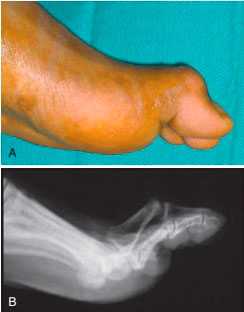

Длительно существующая нестабильность может приводить к развитию деформации пальца типа «лебединая шея», связанной нарушением баланса между сгибателем и разгибателем пальца.

Контрактура суставов и тыльный подвывих большого пальца у профессионального футболиста. А, Внешний вид первого пальца. В, Рентгенограмма в боковой проекции.